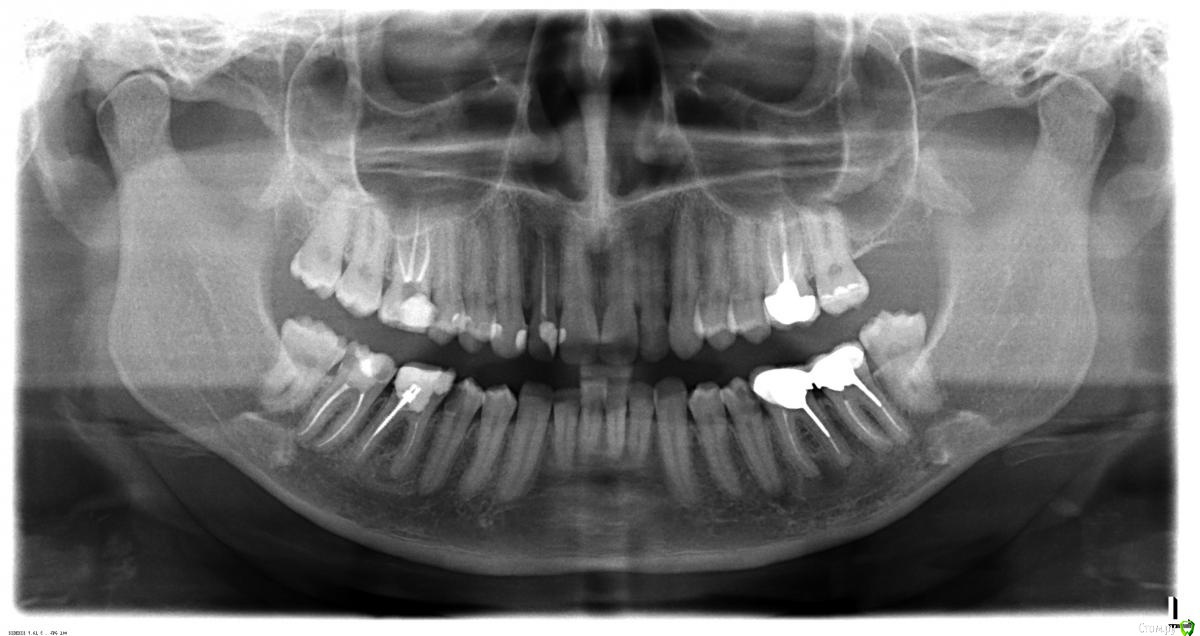

AnnaVA Опубликовано 19 августа, 2018 Поделиться Опубликовано 19 августа, 2018 (изменено) Здравствуйте! Помогите пожалуйста разобраться, что за образование над зубом. Около пяти лет назад случайно обнаружила шишку на десне над зубом (по схеме из интернета зуб 14:-). Диаметр примерно 1 см. Сделала ОПТГ. По ней никто из врачей, щупавших и смотревших шишку, ничего определенного не сказал. Один из хирургов сказал, что ничего страшного, обычная киста от плохого зуба, который следует залечить. Само образование, если не беспокоит, можно не трогать. Собственно меня это образование сильно не беспокоило. Редко поднывало после прогулок в мороз. Не более. По совету хирурга были пролечены все проблемные зубы на этой стороне, однако зуб, над которым располагается шишка, терапевт не стала трогать, мотивировав тем, что выглядит он нормально, а темный цвет обусловлен пломбой, которая в нем находится. За пять лет размер и форма не менялись. На данный момент образование практически не беспокоит, но на одном из снимков видно, что там отсутствует костная ткань. Вопрос: что это за образование и насколько оно опасно? Также на ОПТГ видны гранулемы(?) на нижней челюсти. Одна на корне зуба со штифтом, вторая под зубом с коронкой. Как быть с ними? Терапевт считает, что при попытке вытащить штифт корень сломается. Штифт стоит там уже лет 20. С коронкой все видимо еще сложнее. Зубы не беспокоят. Буду очень признательна за ваше мнение. Есть КТ. Изменено 19 августа, 2018 пользователем AnnaVA Ссылка на комментарий

Bier Опубликовано 22 августа, 2018 Поделиться Опубликовано 22 августа, 2018 темы мы не удаляем.Над 14 зубом ничего не вижу, можете стрелкой показать? Ссылка на комментарий

AnnaVA Опубликовано 22 августа, 2018 Автор Поделиться Опубликовано 22 августа, 2018 темы мы не удаляем.Над 14 зубом ничего не вижу, можете стрелкой показать?Здравствуйте еще раз! Сегодня была у стоматолога. Над 14 зубом воспаления не видно из-за гайморовой пазухи. Убрали старую пломбу и нерв, из-за которого видимо и возникла проблема. Точнее нерв пострадал из-за близкого расположения пломбы. Почистили каналы и заложили лекарство. Будем ждать результат. 1 Ссылка на комментарий

Bier Опубликовано 22 августа, 2018 Поделиться Опубликовано 22 августа, 2018 на нижних зубах грамотный доктор сможет сделать резекцию верхушки с ретроградной пломбировкой.А может и сможет достать штифты. Ссылка на комментарий